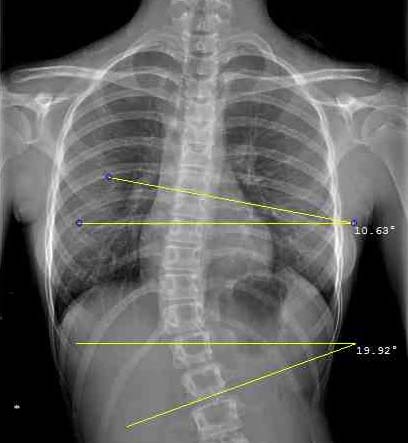

The Cobb angle is calculated drawing firstly two parallel lines tangential the two must tilted vertebrae above and below the curve’s apex and, secondly, two perpendicular lines crossing the tangential ones. The angle is measured at the intersection of the perpendiculars. The inclinometer helps quickly identifying the most tilted vertebrae on radiographs.

On traditional radiographs, the Cobb angle can be drawn using ruler and pencil and measured with a goniometer. The inclinometer can ease the measurement simply placing the tool at the spine’s most tilted vertebra above and beneath the curve’s apex and adding their angle of inclination together.

If radiographs are seen on the computer, the Cobb angle is measured adding together the angles of inclination of the two most tilted vertebrae above and beneath the apex with respect to the horizontal line and using the tools available on the disk (see image).

If the vertebral edge cannot be clearly identified, the tangent to the pedicle is considered the reference point.